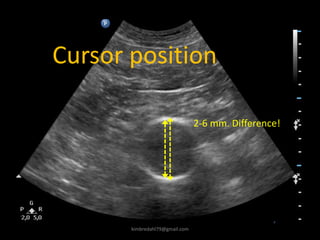

Cursor position

2-6 mm. Difference!

kimbredahl79@gmail.com

Challenges in systoly

Diameter

forskel

Tid

1 sekund

Frame rate = 18

By Henrik Sillesen